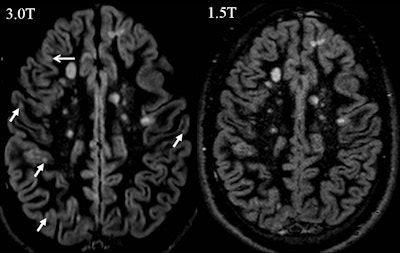

Axial 1.5-tesla and 3-tesla FLAIR obtained in a patients presenting with a clinically isolated syndrome suggestive of multiple sclerosis. Please note that at 3-tesla one juxtacortical lesion could be identified that was not prospectively scored on the 1.5-tesla images.Furthermore, a direct comparison of different magnetic field strengths in terms of diagnostic accuracy is almost impossible. The physical changes occurring when moving to higher magnetic field strength (e.g., tissue relaxation times, specific absorption rate) make it crucial to adjust the pulse sequences and MR protocol in terms of repetition and times, but also require a choice between spatial and temporal resolution to achieve comparable conditions, the authors elaborated. It is arguable whether these conditions are really comparable in terms of a side-by-side 1.5- versus 3-tesla comparison.